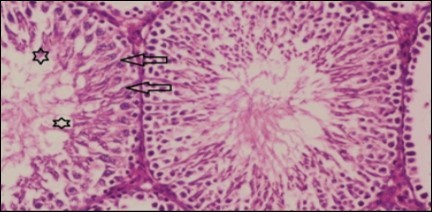

Kidney sections of diabetic rats showed an increase in mesangial cell and matrix of glomeruli with increase in glycogen deposition and hyalinization of arterioles with thickened basement membranes of proximal and distal convoluted tubules. These changes will lead to progressive reduction in the filtration surface of the glomeruli 35. Histological examination of the kidney of the control rats showed normal structure of renal glomerular. The proximal and distal tubules were lined with normal epithelium (Figure 13). The diabetic rats showed tubular casts, inflammatory cellular infiltration and glomerular atrophy (Figure 14). Kidney of rats in groups (3 and 4) showed some glomeruli return to be normal (G). Focal tubules casts (T) in Fenugreek group and some normal tubules in the Glimepiride group with no inflammatory cellular infiltrate in both groups (Figure 15 and Figure 16). However, kidney of rats in group (5) showed normal glomerular (G), normal tubules (T) with no tubular casts (Figure 17).

Figure 14.Photomicrogragh of kidney section of diabetic rat showing a trophy of Bowman,s capsules and damage of glomeruli (arrow) and damage of distal and proximal tubules with congested blood vessels (star) . (H&E) (100Px).

Figure 15.Photomicrogragh of kidney section of treated rat with Fenugreek showing improvement of Bowman,s capsules with normal glomerular (arrow) and nearly return of distal tubules (dashed –arrow) and proximal tubules (star) (H&E) (40xX).

Figure 16.Photomicrogragh of kidney section of treated rat with Glimepiride showing improvement of Bowman,s capsules and partial improvement of glomerulir (arrow) and completely return of distal tubules and proximal tubules to the normal shape with wide urinary space. (H&E) (40X).